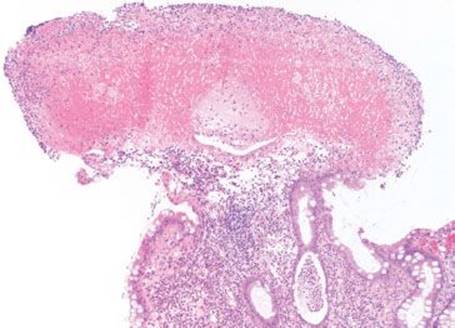

Figure 4.81 Pseudomembranous pattern, early. At scanning magnification, the early pseudomembranes (arrows) are visible as eruptive fibroinflammatory debris along the colonic surface.

Figure 4.82 Pseudomembranous pattern, early. Higher magnification of the previous case shows the fibrin (arrowhead) erupting from the colonic surface amidst numerous neutrophils.